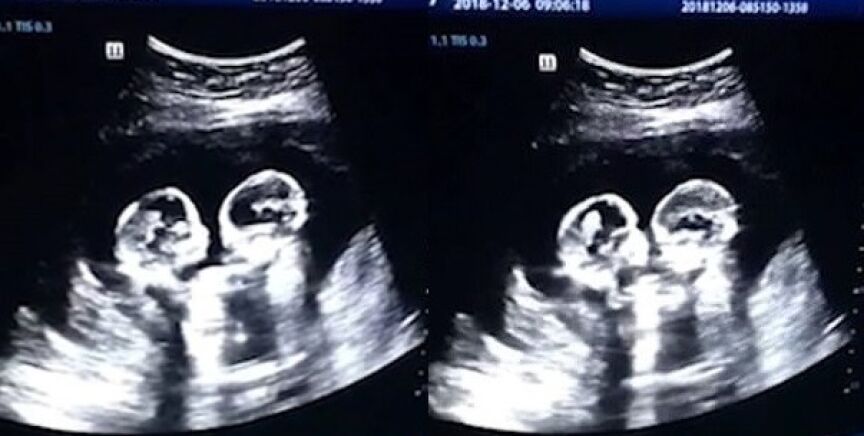

En Yinchuan, China, dos gemelas fueron grabadas el pasado diciembre 'peleándose' dentro del útero durante una revisión en el cuarto mes de gestación, según ha recogido el 'China Daily'.

La ecografía reveló cómo las dos hermanas comenzaban a darse 'patadas' y 'golpes' en el interior de la barriga de su madre.

Las imágenes fueron captadas por el padre de las criaturas, quien se quedó sorprendido ante tal escena. No obstante, según el señor Tao no era la primera vez que veía a las niñas interactuando entre ellas durante una ecografía.

Las gemelascompartían el mismo saco amniótico (gemelos monoamnióticos) por lo que el embarazo era raro y además de alto riesgo. No obstante tenían un 50% de posibilidades después de las 26 semanas y así lo han hecho.